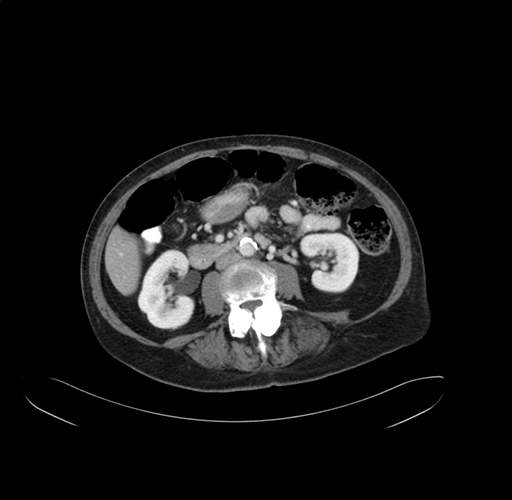

Pre-Chemo: Axial Venous

Axial Venous